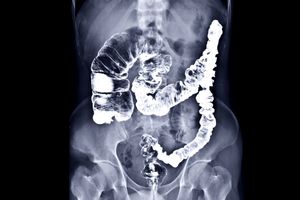

رنگی (Color X-ray)

پرتونگاری رنگی یا با کنتراست رنگی از مواد کنتراست خاص برای افزایش وضوح تصویر استفاده میکند. این مواد معمولاً حاوی یونهای ید یا باریم هستند که در بدن بیمار تزریق یا بلعیده میشوند. این مواد کنتراست کمک میکنند تا قسمتهای خاصی از بدن مانند دستگاه گوارش، عروق و ریهها بهطور واضحتری دیده شوند.ویژگیها:

استفاده از مواد کنتراست که در بدن بیمار وارد میشود تا تصاویر دقیقتری ایجاد کند.

تصاویر بهطور معمول رنگی به نمایش در میآیند.

قادر به نشان دادن جزئیات بیشتر از تصویربرداری ساده.

بررسی و تشخیص مشکلات دستگاه گوارش، مانند انسداد رودهها یا مشکلات معده.

شناسایی ناهنجاریها در سیستم عروقی و مثانه.

بررسی برخی بیماریهای ریوی و قلبی با دقت بیشتر.

بررسی دستگاه گوارش: میتواند به شناسایی مشکلات مربوط به سیستم گوارشی مانند جسم خارجی یا انسداد روده کمک کند.